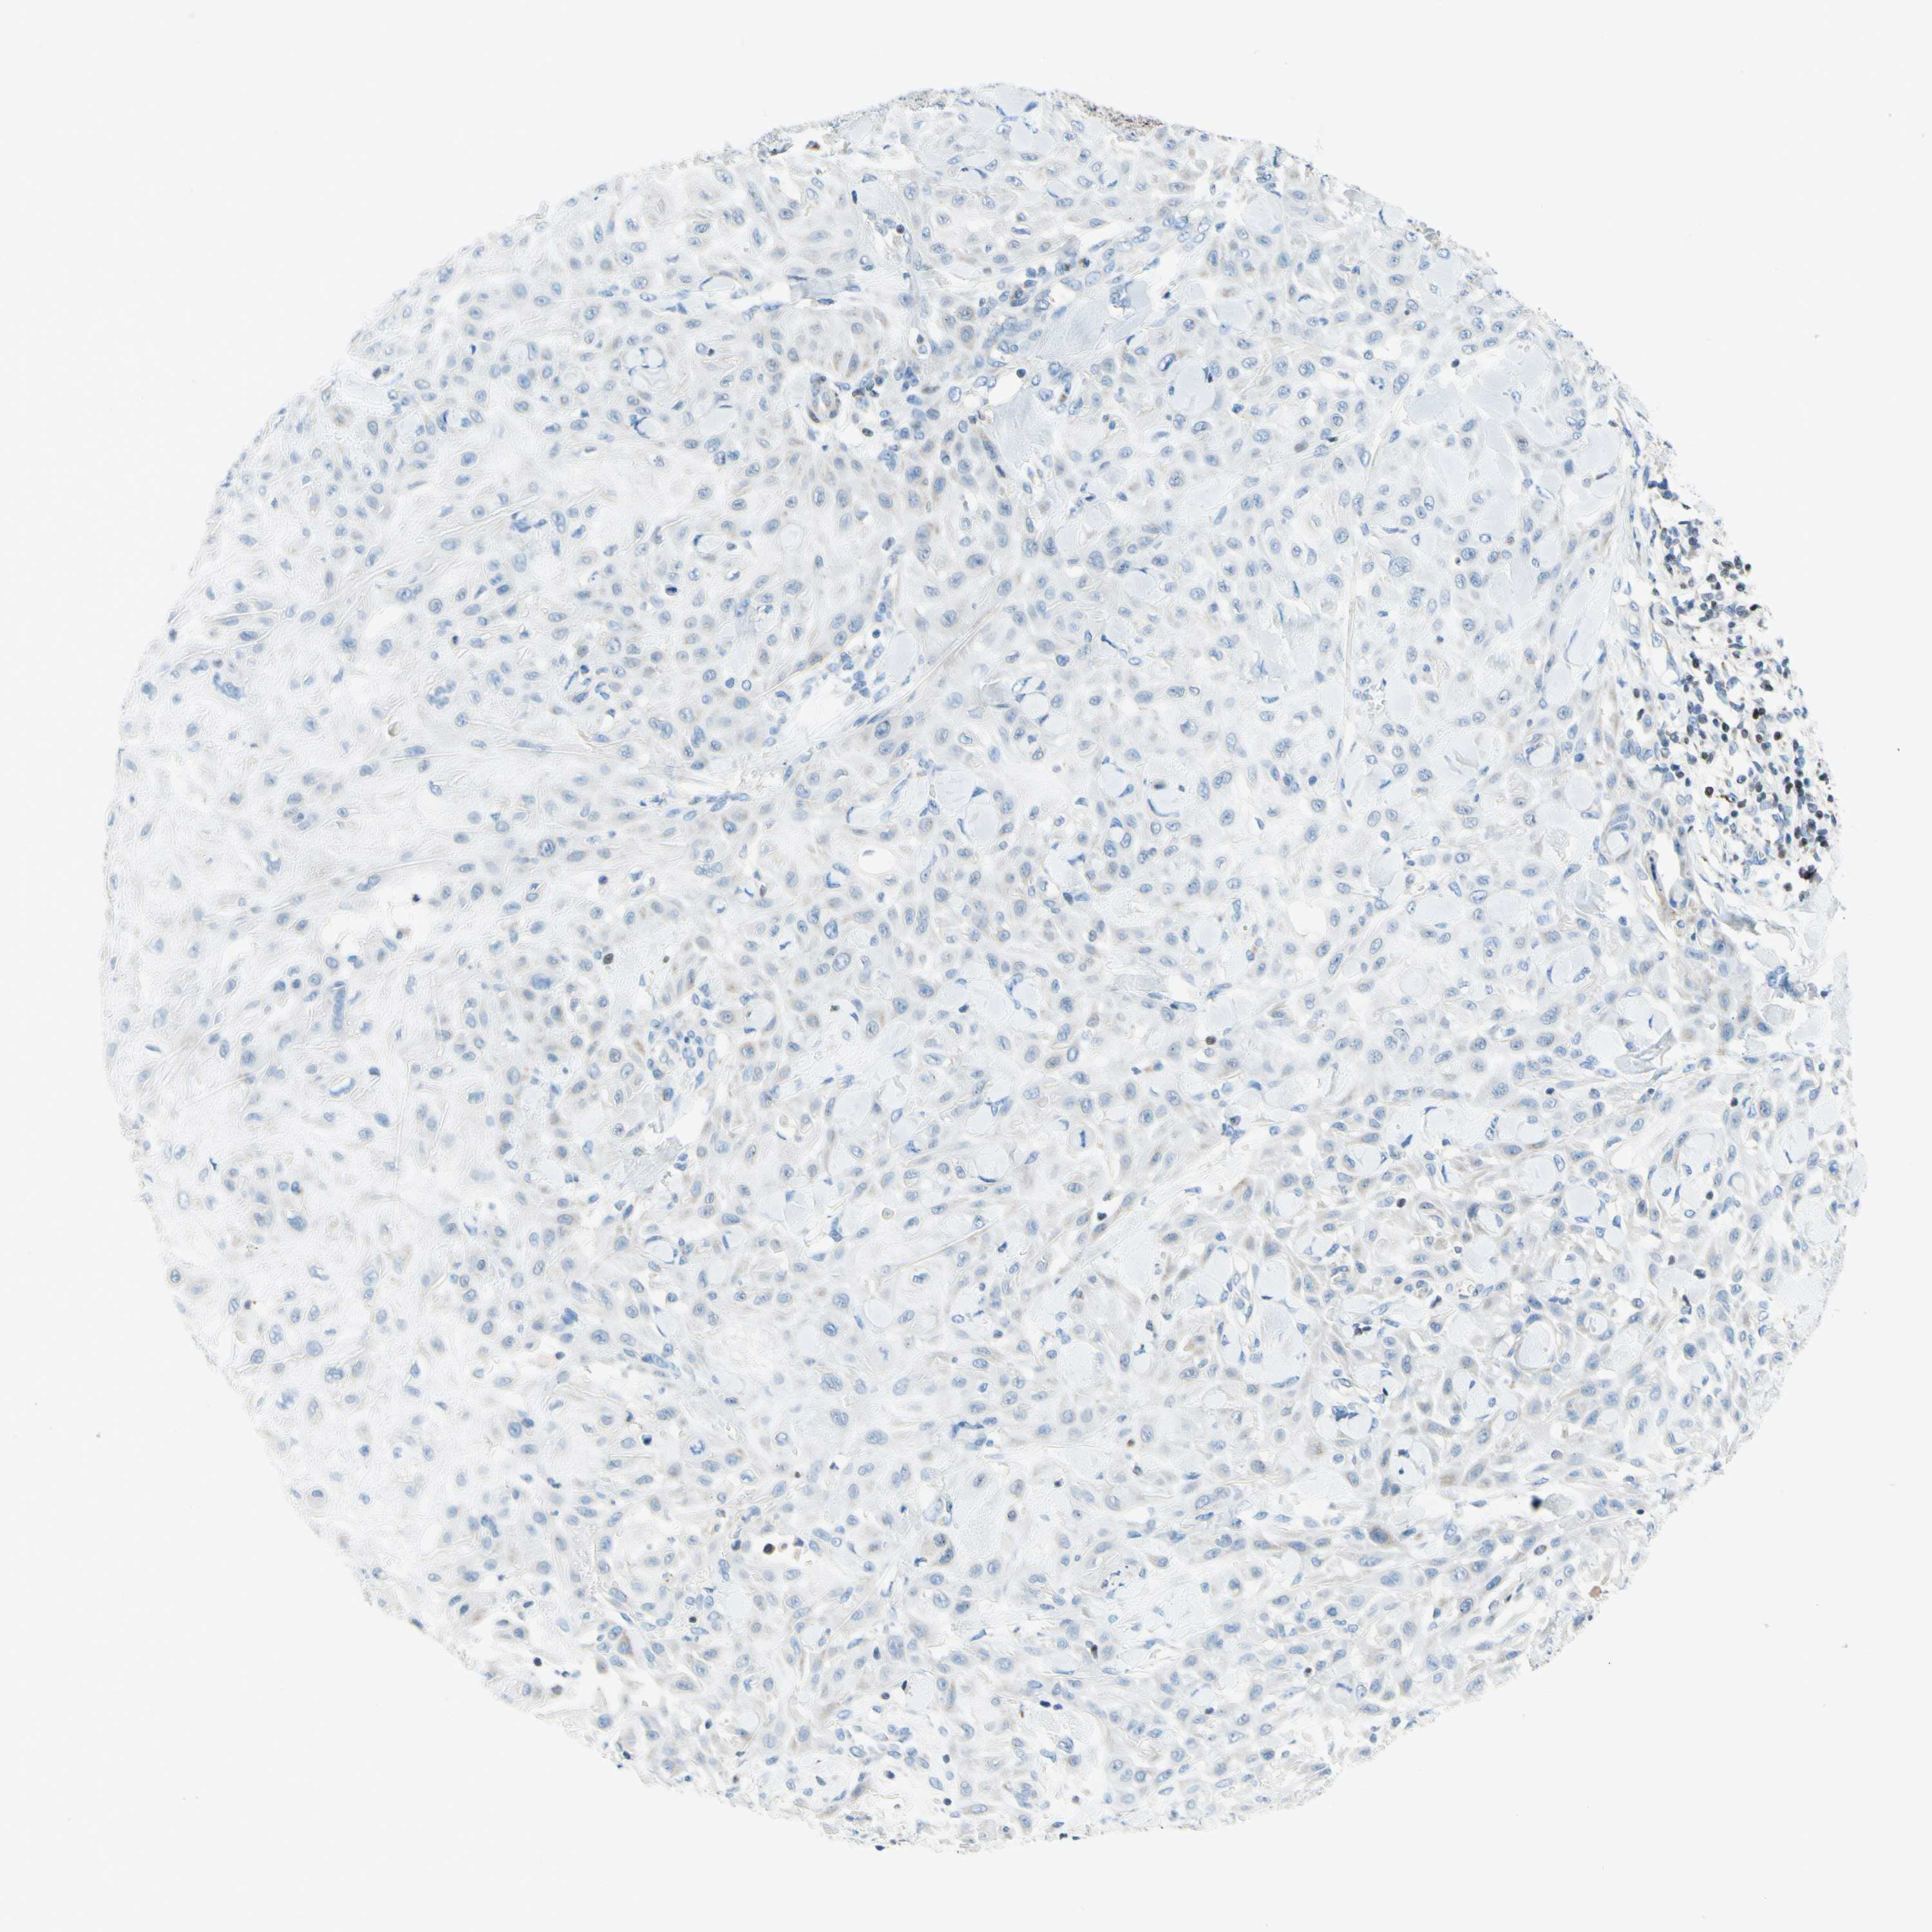

SKIN CANCER - Protein expressioni

A mouse-over function shows sample information and annotation data. Click on an image to view it in a full screen mode. Samples can be filtered based on level of antibody staining by selecting one or several of the following categories: high, medium, low and not detected. The assay and annotation is described here.

Antibody stainingi

Antibody staining in the annotated cell types in the current human tissue is reported as not detected, low, medium, or high, based on conventional immunohistochemistry profiling in selected tissues. This score is based on the combination of the staining intensity and fraction of stained cells.

Each image is clickable and will lead to virtual microscopy that enables deeper exploration of all samples and also displays staining intensity scores, fraction scores and subcellular localization as well as patient and tissue information for each sample.

Antibody HPA048677

Staining

Not detected

Negative

None

Basal cell carcinoma